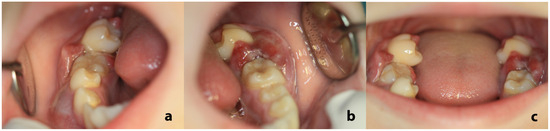

| 44 | Papadopoulou et al., 2024 (present case) | 11 | F | Painful swellings of the gingiva of the lower molars, tooth hypermobility, and facial asymmetry | Bilateral gingival swellings (erythematous and focally ulcerated) adjacent to mandibular premolars and molars that were hypermobile, displaced, and partially extruded Facial swelling along the right posterior mandible | Panoramic radiograph: ill-defined radiolucencies in the posterior mandible bilaterally, ‘floating-in-air’ teeth appearance CT: hypodense masses along and distal to the mandibular ramus extending upwards into the maxillary sinuses bilaterally, and the posterior wall of the right orbit; perforation of the right mandibular cortex | 11 years, no recurrence |